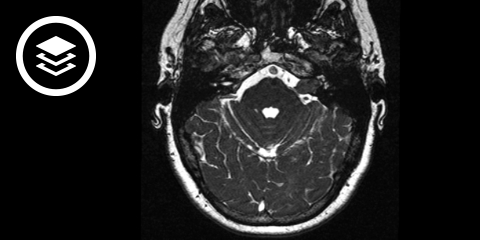

MRT-Fallbeispiel

- Bildquelle DICOM-Viewer: Kujawa et al.(2023). Segmentation of Vestibular Schwannoma from Magnetic Resonance Imaging: An Annotated Multi-Center Routine Clinical Dataset (Vestibular-Schwannoma-MC-RC) (Version 1). The Cancer Imaging Archive.